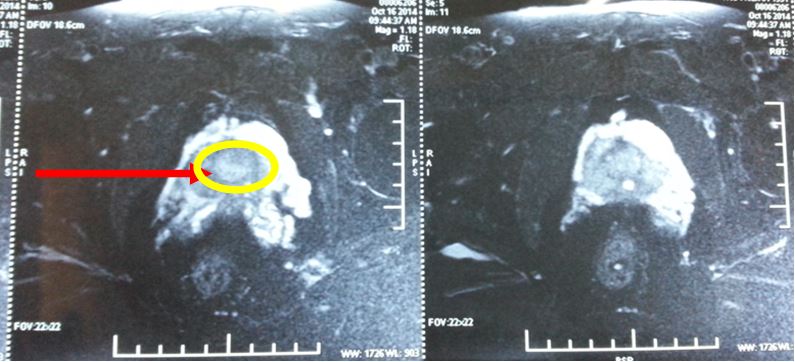

Trên hình ảnh MRI, khối u tuyến tiền liệt ranh giới rõ, bắt thuốc mạnh, kích thước 15 mm, chưa xâm lấn vỏ bao và túi tinh 2 bên.

- Chụp MRI: Không thấy khối bất thường trên hình ảnh MRI tiểu khung

Trước điều trị: khối u tuyến tiền liệt ranh giới rõ, bắt thuốc mạnh, kích thước 15 mm, chưa xâm lấn vỏ bao và túi tinh 2 bên; PSA = 28,5 ng/ml

Sau điều trị 7 tháng: không còn u trên cộng hưởng từ, nồng độ PSA về bình thường, bệnh nhân hết đi tiểu khó, thể trạng tốt; PSA giảm xuống rất nhiều còn 0,91 ng/ml.